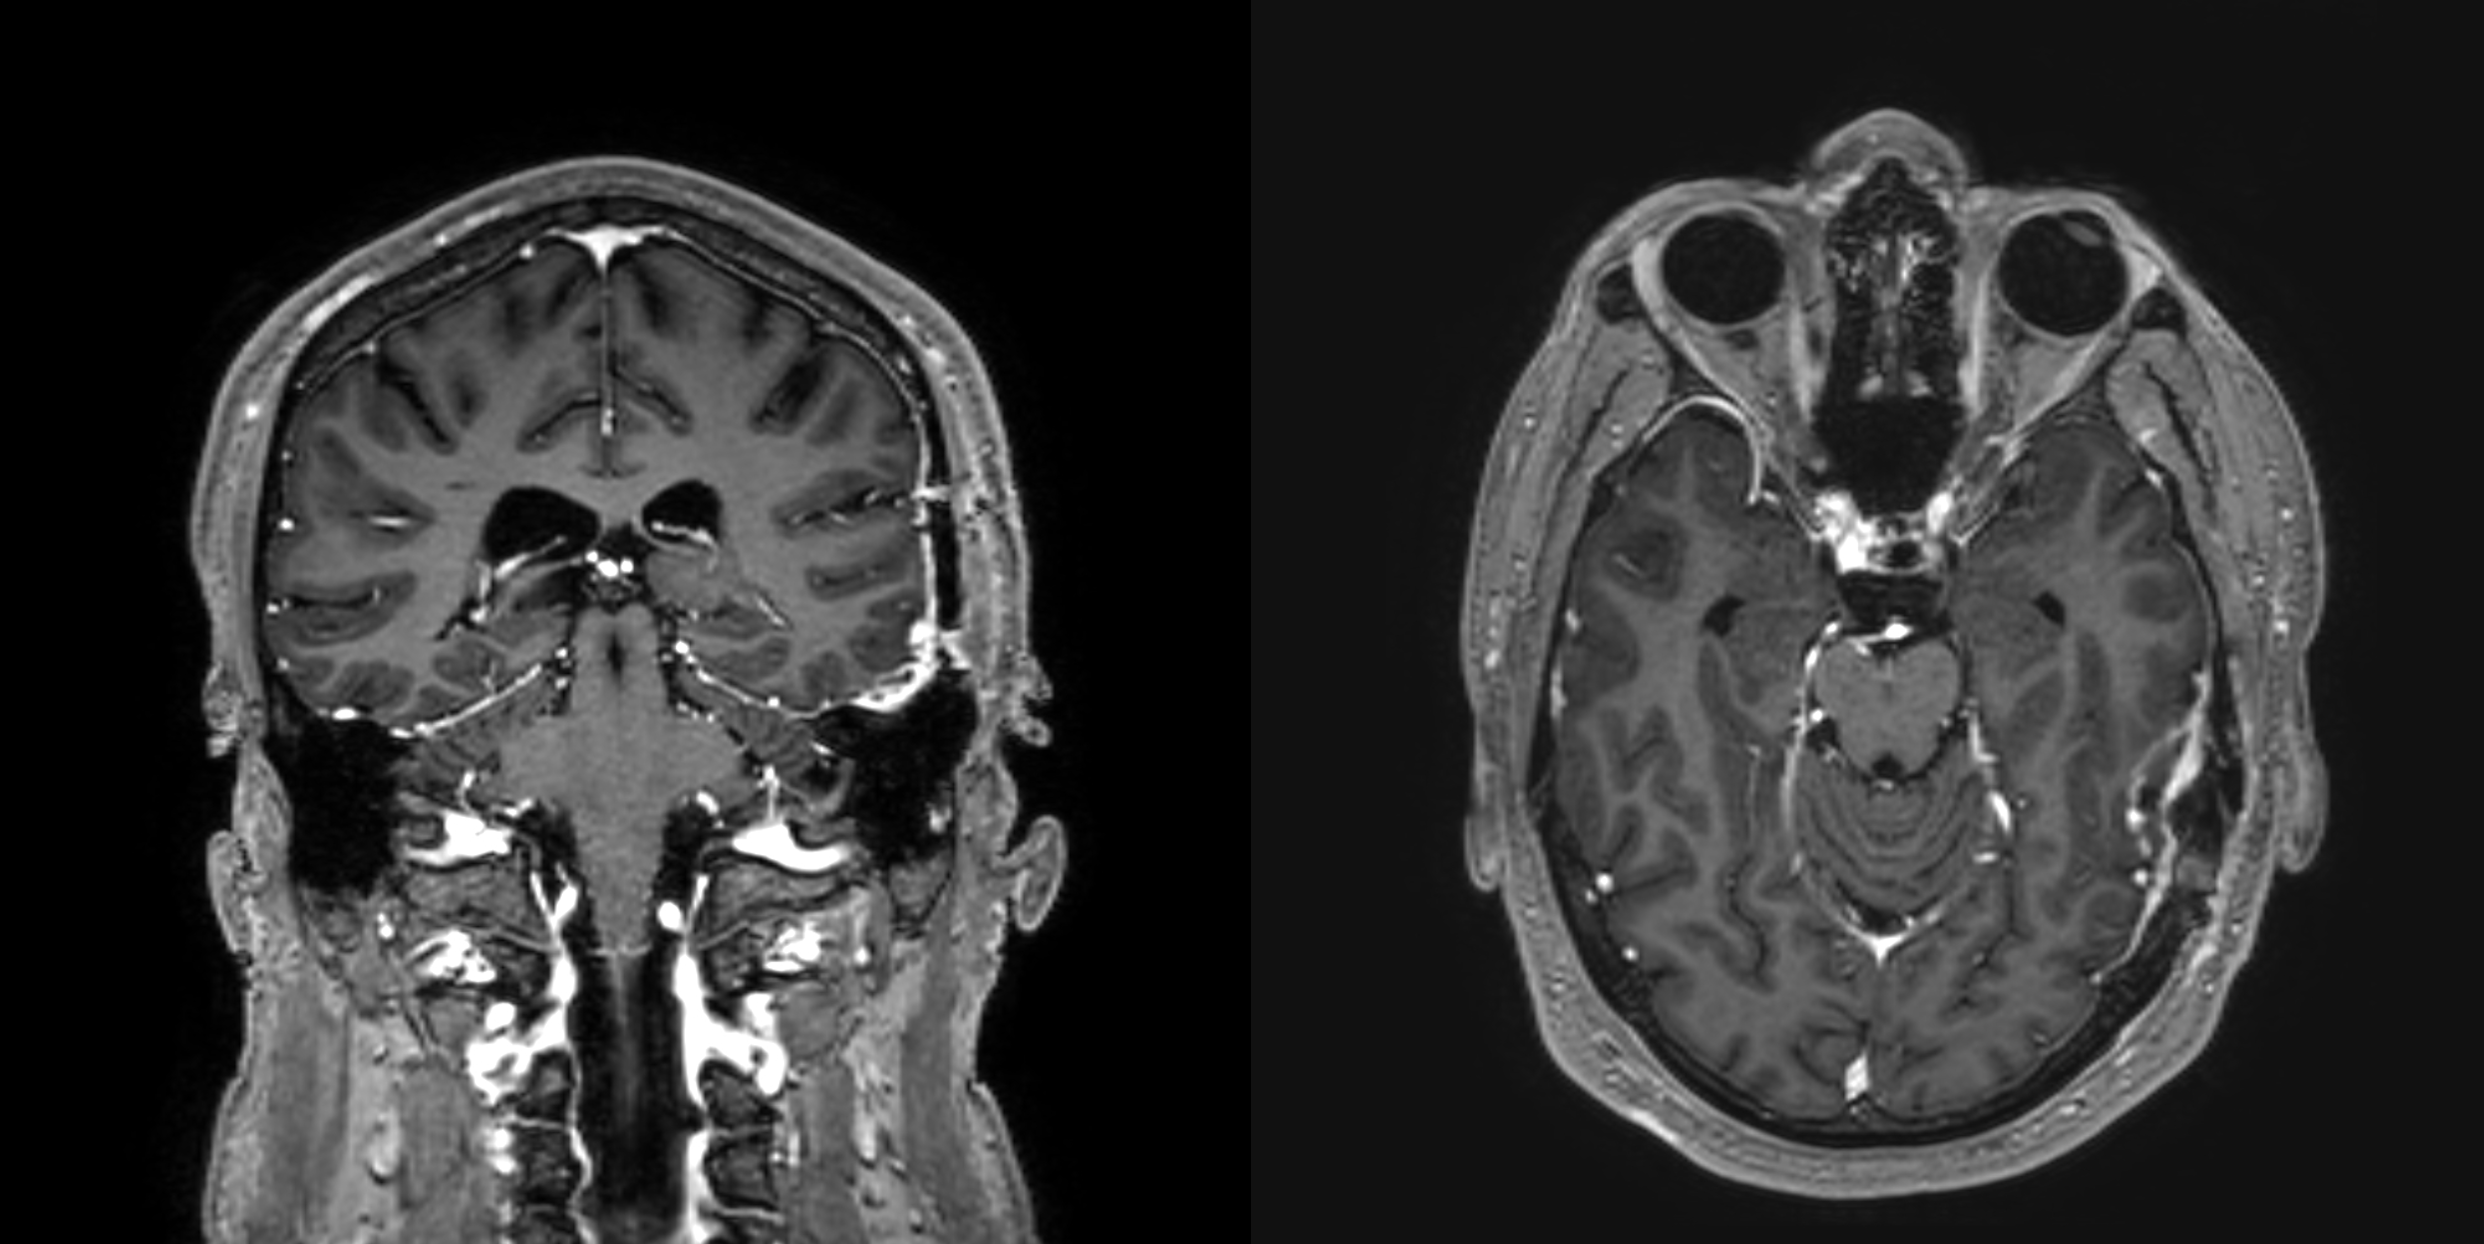

Background

This study explored whether Myelin Water Imaging could detect myelin injury in Anti-NMDA receptor autoimmune encephalitis (NMDAr-AIE), where traditional neuroimaging is often normal. Myelin Water Fraction (MWF) quantifies myelin content by distinguishing myelin sheath water from other brain water compartments.

Methods

Adult participants with confirmed NMDAr-AIE diagnoses and healthy controls (HC) underwent 3T brain MRI (Magnetic Resonance Imaging) including MWF mapping. Participants were recruited after discharge from the hospital. Mean MWF was calculated for 4 white matter regions of interest (ROI). MHI (Myelin heterogeneity Index) was calculated by dividing the MWF standard deviation by the mean MWF. Patient demographics, clinical assessments, treatment, and outcomes were collected.

Results

Five participants with NMDAr-AIE (4F/1M, mean age 30, SD 7) and four HC (3F/1M, mean age 36, SD 6) were included. All NMDAr-AIE participants had normal or non-specific T2 hyperintensities on initial imaging and had received immunotherapy. The mean Modified Rankin Score (MRS) on discharge was 2. MWF (mean ± SD) for normal-appearing white matter, corpus callosum, corticospinal tract, and superior longitudinal fasciculus were 0.10±0.02, 0.12±0.02, 0.15±0.03, 0.12±0.02, which were very similar to HC at 0.09±0.02, 0.11±0.01, 0.15±0.02, and 0.11±0.02, respectively.

Fig. 1 Myelin Water Imaging of two selected patients

Screenshot 2025 06 01 at 12.05.23 pm

Conclusions and Future Direction

Myelin Water Imaging showed no myelin pathology in five NMDAr-AIE patients, with MWF and MHI values comparable to HC, suggesting that myelin pathways are relatively preserved post-recovery from AIE. Moving forward, we aim to continue recruiting healthy controls, patients post-recovery and those experiencing active disease to determine if there are any MWF abnormalities throughout the disease course. Future studies are needed to assess MWF changes in other antibody-mediated encephalitides.